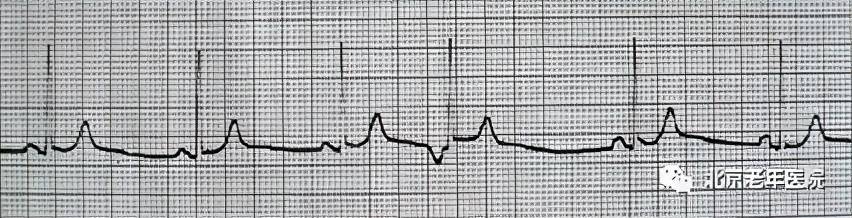

早搏,就是心脏在正常跳动节奏之外提前收缩的现象,这种情况可能会让我们感觉到心慌、胸闷,甚至有一种心脏要跳出胸膛的感觉,不过,大多数早搏都是良性的,只要保持良好的生活习惯,一般都能自行缓解。